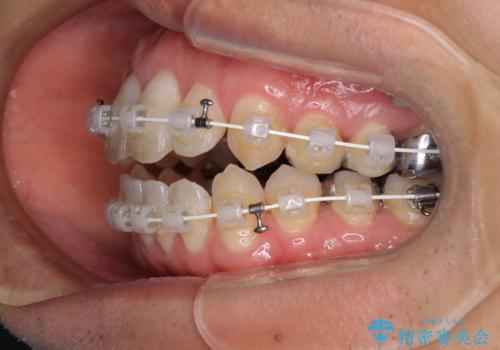

- 矯正装置

- 審美装置

上顎奥歯付近にアンカースクリューを用い、上顎歯列全体の後方移動と、大臼歯圧下を促し、前歯の上下関係を改善することとしました。